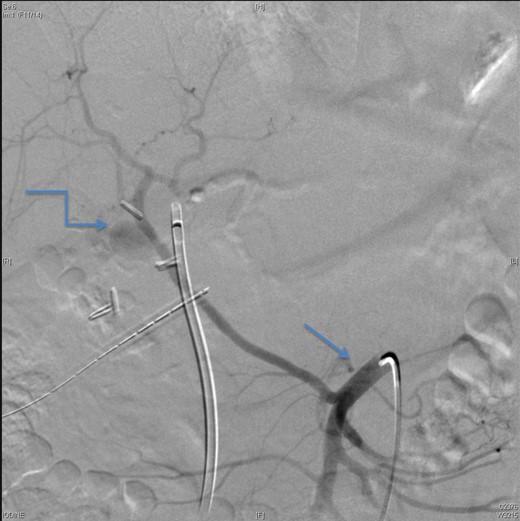

Upon presentation to our center, the patient was febrile (38.9°C) and complained of a left upper limb pain and swelling. The surgical drain was draining a mixture of bile and blood. His WBC count was 14 × 109/l, total bilirubin 35 µmol/l and the direct bilirubin 21 µmol/l. A duplex ultrasound of the upper limb revealed a left brachial vein thrombosis. Hematology was consulted, and a diagnosis of acute upper limb venous thrombosis was established. Owing to the presence of blood in the drain, he was kept on the maximum prophylactic dose of unfractionated heparin. A CT angiography of the abdomen showed two collections, one at the surgical bed near the drain, and the other was subcapsular below the left lateral lobe of the liver, as well as an aneurysm of the replaced right hepatic artery with an active bleeding blush (Fig. 1). The patient was immediately referred for an angiography, which confirmed the CT scan findings (Fig. 2). An arterial stent was inserted at the location of the aneurysm (Fig. 3), and a pigtail drain was inserted to drain any residual collection. An ERCP was also performed, which revealed a Strasberg Class D injury, and a plastic biliary stent was inserted. After the angio-stent insertion and stabilization of the patient, heparin infusion was started. Five days later he developed hematemesis and melena with a significant drop in his Hb to 2 g/l, and his total bilirubin became 183 μmol/l of which 91 μmol/l is direct. A gastroscopy was performed and showed hemobilia (bleeding from the ampulla of Vater). Subsequent angiography demonstrated a leak of contrast just above the arterial stent; hence, a further stent was placed to cover that area of the aneurysm. Similar symptoms reoccurred a week later, and a new angiography showed a new aneurysm from the left proper hepatic artery. A percutaneous thrombin injection of the aneurysm was performed as the bleeding branch was unreached via direct angiography and was filling in retrograde perfusion. During recovery a chest spiral CT was performed, which revealed the diagnosis of a bilateral segmental pulmonary embolism. Heparin infusion with low targets of partial thromboplastin time of 50–60 was started.

An angiographic scan showed stent in the replaced right hepatic artery.